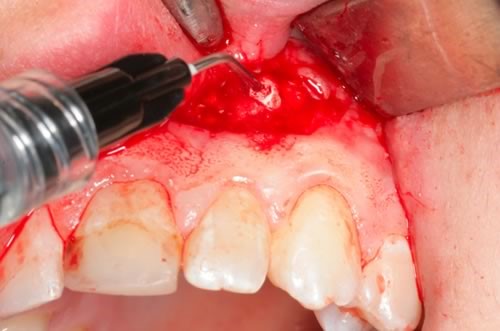

Если гранулемы не рассасываются, то нужна резекция верхушки корня зуба. Доступ к ней осуществляется через разрез на десне с выпиливанием участка кортикальной пластинки челюстной кости. После иссечения верхней трети корня возможно ретроградное пломбирование канала. В послеоперационном периоде регенерация костной ткани занимает в среднем 1 месяц.